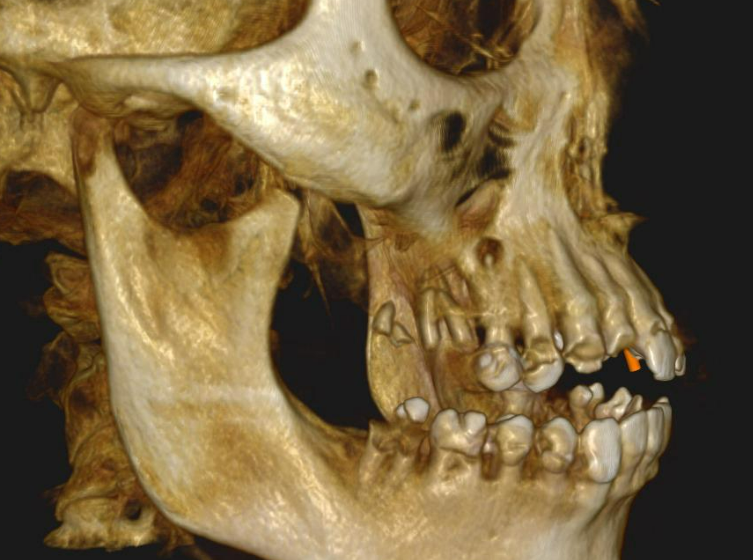

Long-term psychoactive substance use had caused severe xerostomia, contributing to the rapid development of dental caries and decay. The teeth in the upper jaw were non-restorable, and many were already missing. The condition of the lower jaw was slightly better: the anterior teeth were in satisfactory condition, but the posterior teeth were severely decayed and required extraction.

The presented images show the patient’s initial dental condition.